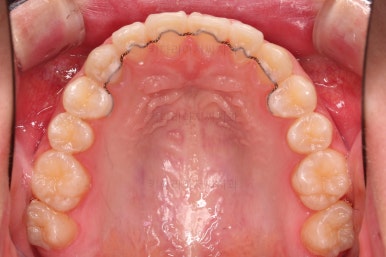

악궁확장 이 후 브라켓을 부착합니다.

이번 환자분이 선택하신 장치는 엠파워 클리어라고 하는 자가결찰 세라믹 장치인데요.

철사를 스스로(자가) 묶을 수(결찰) 있는 뚜껑이 달린 세라믹 성분의 장치입니다.

대표적인 장치가 클리피씨 장치이며 클리피는 일본회사, 동래교정치과 키다리아저씨치과가 쓰는 엠파워는 미국회사라는 차이가 있고 큰 틀에서는 동일한 계열의 장치입니다.